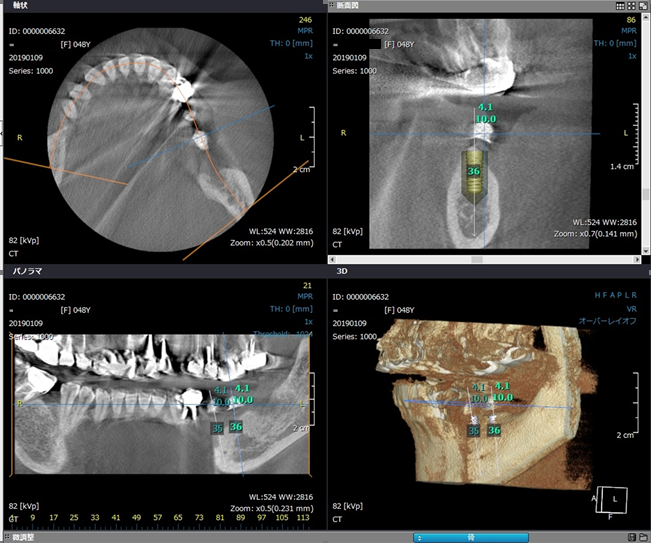

歯科用CTを使用すれば、骨の構造を立体的にはっきりと把握することが可能です。

CT撮影した患者様の顎骨の形をデジタルデータで取り込んで、神経や血管の位置、骨の強度までを調べることができ、神経や血管を傷付けることなく、インプラントを埋め込むことが可能となりました。

安全で正確なインプラント手術のためには、歯科用CTは欠かすことができません。